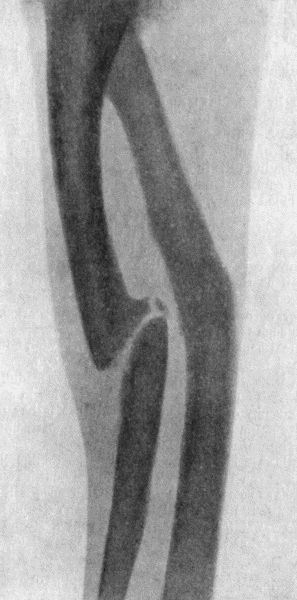

89.Radiogram of Transverse Fracture of both Bones of Leg by Direct Violence178

90.Radiogram of Oblique Fracture of both Bones of Leg by Indirect Violence178